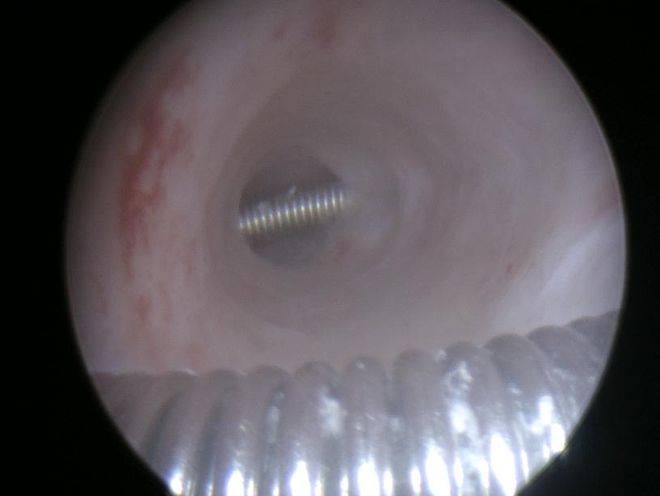

主管医生很快给患者很快安排了麻醉下宫腔镜取环。待放入宫腔镜检查后发现环已经完全嵌入了子宫的肌层中,把一个环分成了四段,我们可以见到其中的两段。医生在宫腔镜直视下放入取环钩,看看能不能把环带出来,结果在往外带的过程中,暴露部分的环断裂了,埋在子宫肌层的环却丝毫未动。出不来怎么办?只能改变策略——上大家伙了。医生非常困难地把宫颈扩张到9号,放入了电切镜,针状电极定位切开宫腔两侧覆盖住环的子宫肌层,环一下子被松解开来就到了宫腔里,终于顺利地夹出了环。接下来取了内膜活检,电凝止血,手术非常顺利的结束了。